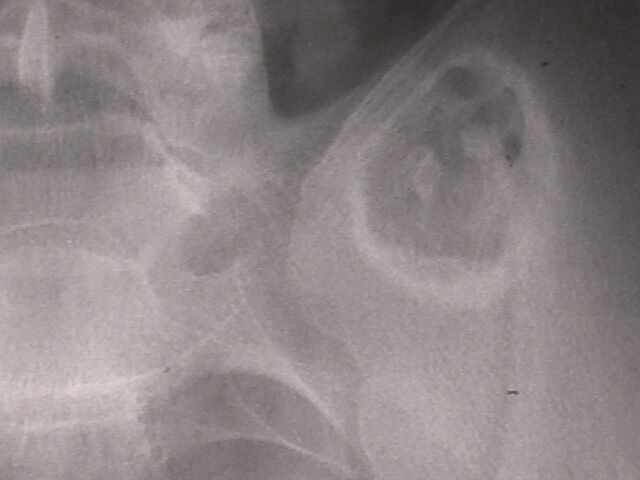

У сына ( 18 лет) медицинской сестры, во время обследования в военкомате на рентгенограмме выявлена опухолевидное образование, клинически бессимптомное.

Больной консультирован в Новосибирском онкологическом диспансере, областной консультативной поликлинике. Поставлен диагнозэнхондрома левой подвздошной кости. Рекомендовано наблюдение контрольное рентгенологическое обследование через год. По-моему лучше бы опухоль назвать экхондромой (рост преимущественный вне кости). Считаю, что лучше предложить оперативное лечение- удаление опухоли Прошу коллег высказать свое мнение. Если необходимо оперативное лечение - где можно его осуществить.

Опухоль выглядит очень продолжительной, хорошо инкапсулированной. Думаю, решение Н-Сиб. онкологов умно и резонно. Если клинически это образование не проявляется и через 1,5-1 год не растет и не перерождаетсято лучше его не трогать. Вы ведь знаете ,что вылущивание опухоли в этом районе не просто, есть возможность конфликта с Sacro-Ileac Joint и с пояс.-крестц. нерв. сплетением. Бессимптомным из этой операции молодой парень, на мой взгляд, не выйдет. И всего хуже, Вам ведь известно, после удаления остатки опухоли (всегда есть остатки!) часто малигнизируют. Мой совет звучит лучше по-украински: не чапай беды.

Посмотрели с коллегой из ортопедического отделения, где как раз доброкачественными опухолями скелета занимаются. Желательно бы

дообследовать пациента - уточнить на КТ форму, размеры и локализацию, показать опытным рентгенологам. Как-то странновато образование

пересекает крестцово-подвздошный сустав.